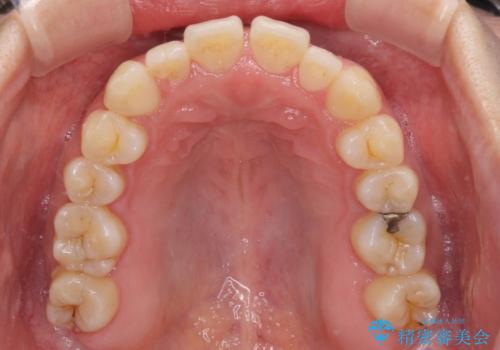

すきっ歯とオープンバイトをインビザラインで改善

- 前歯の上下スペースと前歯の隙間を気にして来院された患者様です。

インビザラインにより上下の前歯の隙間を閉じていくこととしました。

上下の隙間に舌が入り込むことが、すきっ歯やオープンバイトの原因であったため、舌の筋肉のトレーニングも並行して行い、後戻りの抑制を図りました。